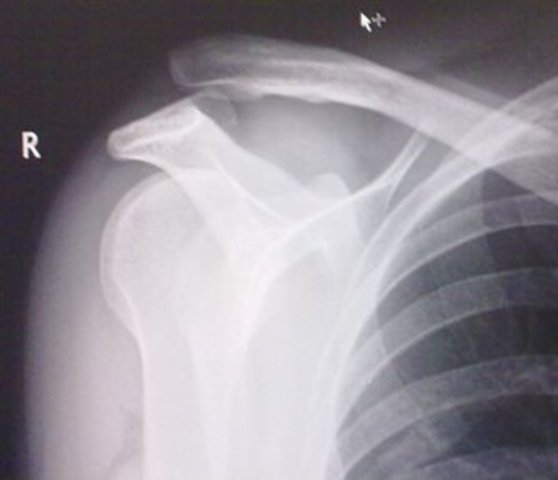

• Dislocated Clavicle

Dislocated Clavicle

in Jr. High I did a front-flip and I landed on my shoulder and dislocated my clavicle and torn a ligament.